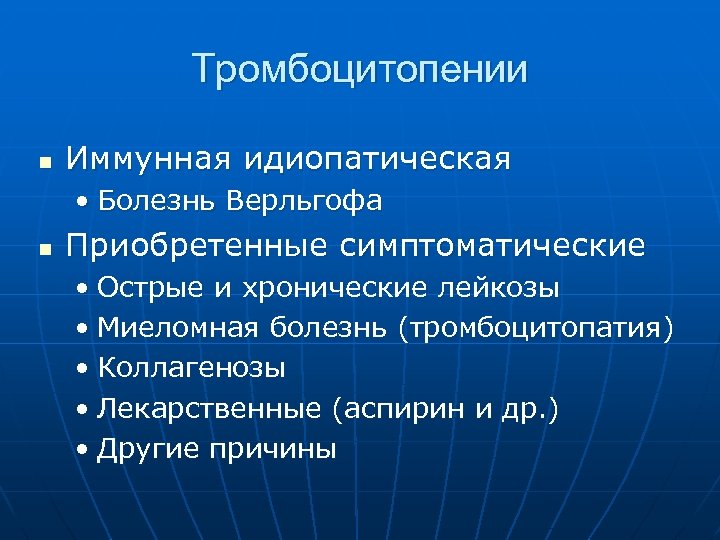

Тромбоцитопении n Иммунная идиопатическая • Болезнь Верльгофа n Приобретенные симптоматические • Острые и хронические лейкозы • Миеломная болезнь (тромбоцитопатия) • Коллагенозы • Лекарственные (аспирин и др. ) • Другие причины